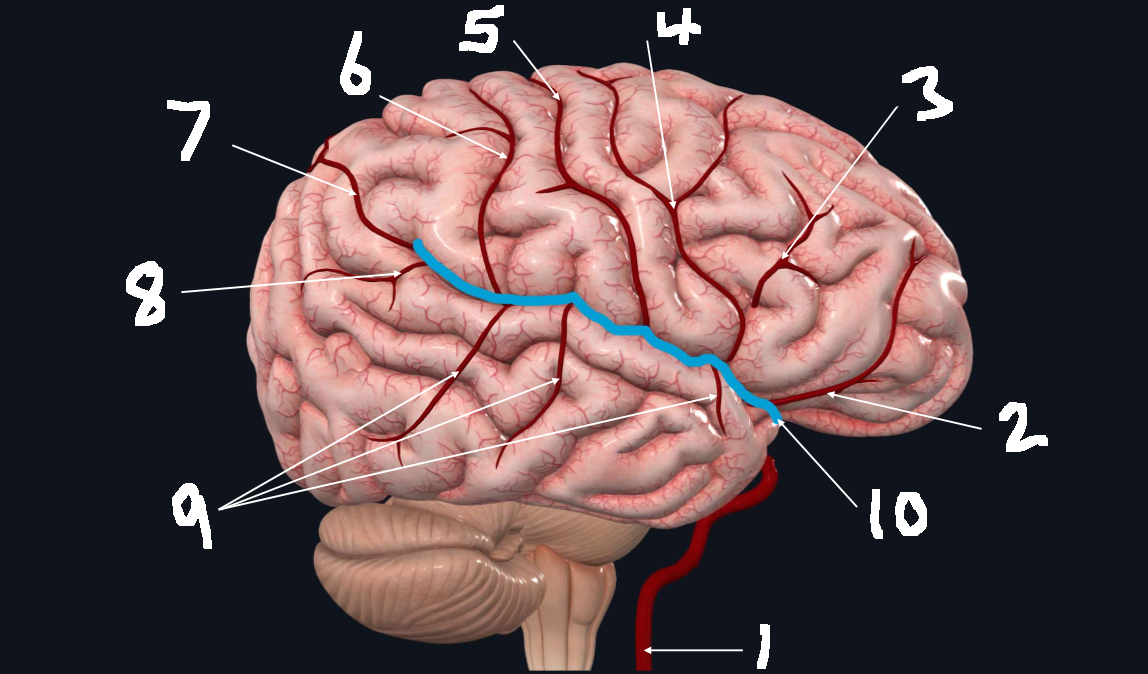

What is 1?

internal carotid artery

What is 2?

orbitofrontal artery

What is 3?

prefrontal artery

What is 4?

precentral artery

What is 5?

central artery

What is 6?

postcentral artery

What is 7?

posterior parietal artery

What is 8?

angular artery

What is 9?

temporal arteries (anterior, middle, posterior)

What is 10?

lateral cerebral fissure